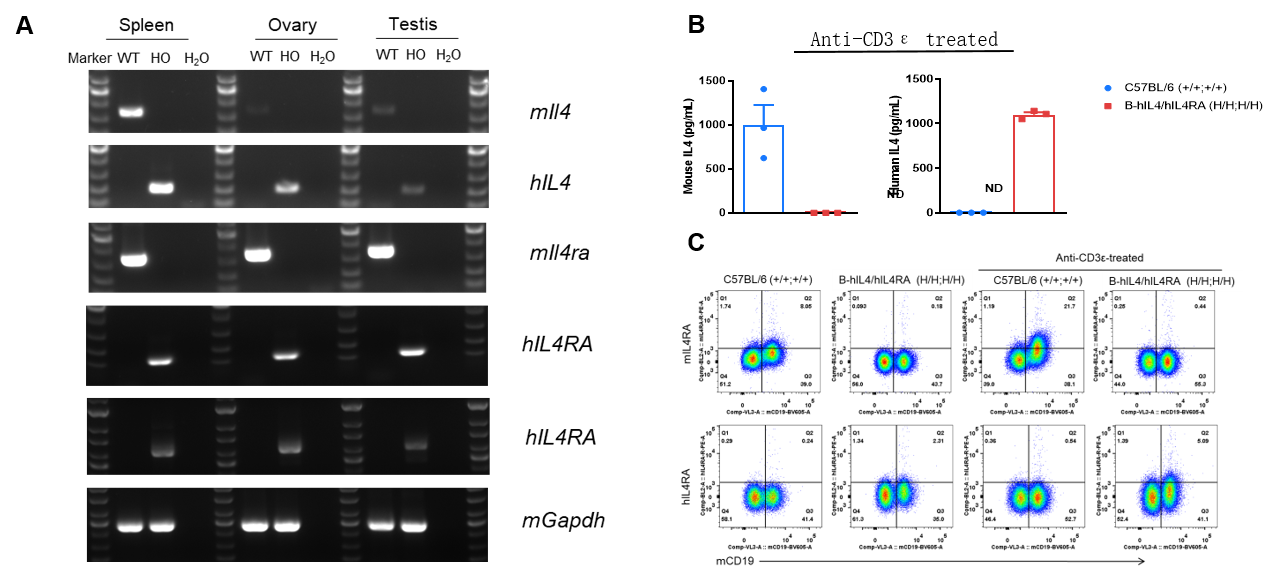

Strain specific analysis of IL4 and IL4RA gene expression in WT and B-hIL4/hIL4RA mice. (A) Mouse Il4 and Il4ra mRNA were detectable in spleen, ovary and testis of wild-type mice. Human IL4 and IL4RA mRNA were detectable only in homozygous B-hIL4/hIL4RA mice but not in wild-type mice. (B) Serum were collected from WT and homozygous B-hIL4/hIL4RA mice stimulated with anti-CD3ε in vivo, and analyzed by ELISA with species-specific IL4 ELISA kit. Mouse Il4 was detectable in WT mice. Human IL4 was exclusively detectable in homozygous B-hIL4/hIL4RA mice but not WT mice. (C) Splenocytes were collected from WT and homozygous B-hIL4/hIL4RA mice, and analyzed by flow cytometry with species-specific anti-IL4RA antibody. Mouse Il4ra was detectable in WT mice. Human IL4RA was exclusively detectable in homozygous B-hIL4/hIL4RA mice but not WT mice.